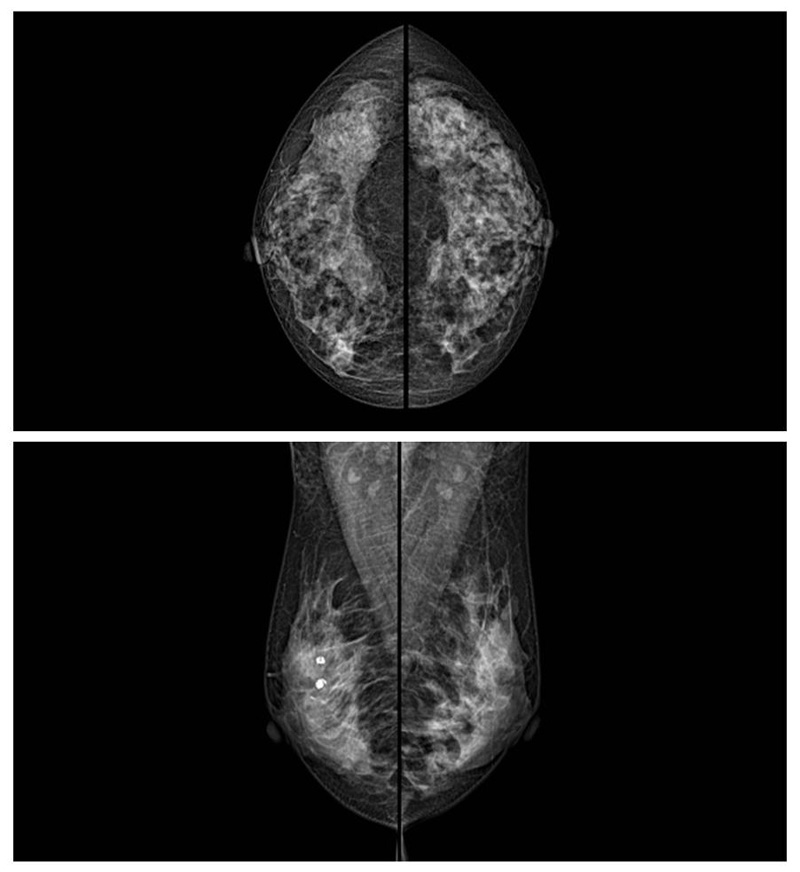

乳腺癌的發生率越來越高,已經是秋葵视频男人的加油站國家的癌症之一已成為女性健康“頭號殺手”。乳腺DR可提高乳腺癌早期檢出率並精準定位。發現和診斷早期乳腺癌最有效的方法之一,明顯利大於弊女性都要重視乳腺的檢查。輻射很小最簡便、最可靠、無創性檢查手段,做一次乳腺DR的劑量相當於7周的正常生活。尤其是對於40歲以上的女性尤為重要,那麽乳腺DR是怎麽進行檢查的呢?秋葵视频男人的加油站來了解一下,為廣大朋友在檢查前有點心理準備。檢查時候是避開經期的前後,月經來後的7天左右比較合適。需要脫衣服檢查,根據拍片的擺位要求,有頭尾位置,內外斜位,還有側位。定點放大壓迫方法可以更細微清晰的檢查出病灶。